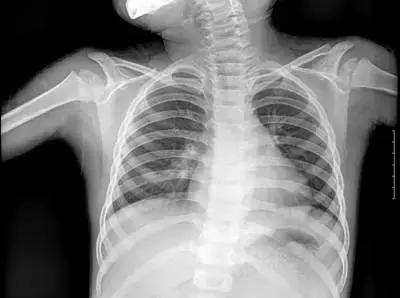

但人体各组织结构的密度不同,X线穿透时被吸收的量不同,就形成了黑白灰分明、层次显著的“片子”。看图举例子:

▲X射线成像图

骨骼、钙化灶、体内液体等(听起来质地较厚重的组织),吸收X光较多,因此形成白色影像,也就是传说中的“高密度影”,上图的上臂、肋骨就是如此。

呼吸道、胃肠道、脂肪组织(听起来质地较疏松),吸收X光较少,在片子上呈现黑色影像,即“低密度影”,图中含气体较多的肺脏是代表。

再就是密度居中的实质器官、 肌肉、结缔组织,比如心脏,在片子上呈现的影像介于黑白两色之间。

X光片“泾渭分明”的特点帮医生辨别身体的不同病变。

骨折、肋骨病变,密度高的骨骼白色影像哪里出问题一目了然,比如液气胸等肺部及气道病变,肺脏的黑色影像中就会混入明亮的白色。